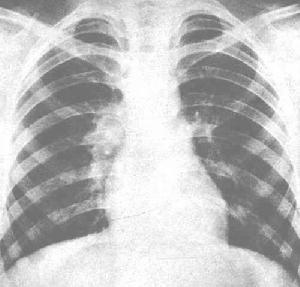

對確定肺結核病灶的性質、部位、範圍及其發展決定治療方案等具有重要作用,是診斷小兒肺結核的重要方法之一。最好同時作正、側位胸片檢查,對發現腫大淋巴結或靠近肺門部位的原發病灶,側位片有不可忽視的作用。

(1)原發綜合徵:肺內原發灶大小不一。局部炎性淋巴結相對較大而肺部的初灶相對較小是原病性肺結核的特徵。嬰幼兒病灶範圍較廣,可占據一肺段甚至一肺葉,年長兒病灶周圍炎症較輕,陰影範圍不大,多呈小圓形或小片狀影,部分病例可見局部胸膜病變。小兒原髮型肺結核在X線胸片上呈現典型啞鈴狀及雙極影者已少見。

(2)支氣管淋巴結結核:是小兒原髮型肺結核X線胸片最為常見者。分三種類型:①炎症型:淋巴結周圍肺組織的滲出性驗炎性浸潤,呈現從肺門向外擴展的密度增高陰影,邊緣模糊,此為肺門部腫大淋巴結陰影,②結節型:表現為肺門區域圓形或卵圓形緻密陰影,邊緣清楚、突向肺野,③微小型:是逐漸被重視的一型,其特點是肺紋理紊亂,肺門形態異常,肺門周圍呈小結節狀及小點片狀模糊陰影,此型應緊密結合病史、臨床表現及其他有關檢查等分析,以免漏診。CT掃描可顯示縱隔和肺門淋巴結腫大,對疑診肺結核但胸部平片正常病例有助於診斷。